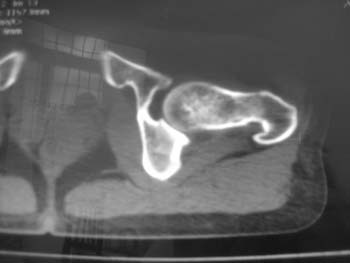

以下是引用358450m在2008-8-12 12:12:00的发言:[br]骨囊肿

以下是引用yangyudong333在2008-8-12 14:30:00的发言:[br]考虑退京变所致关节面下骨质囊变

以下是引用随光逐影在2008-8-12 20:40:00的发言:[br]考虑邻关节骨囊肿或骨内腱鞘囊肿。